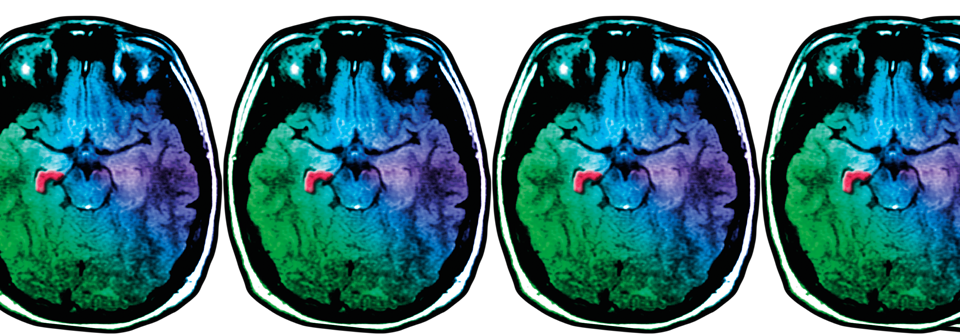

Jeder Patient mit einem ersten Krampf­anfall sollte eine MRT erhalten, um strukturelle Läsionen wie eine Hippo­campussklerose (rot) zu erkennen.

Jeder Patient mit einem ersten Krampf­anfall sollte eine MRT erhalten, um strukturelle Läsionen wie eine Hippo­campussklerose (rot) zu erkennen. © Science Photo Library/Living Art Enterprises, LLC